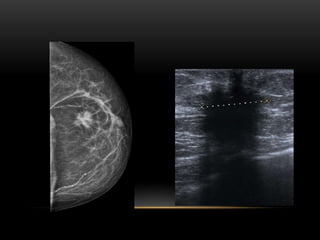

CATEGORIA BI-RADS: 4A

Probabilidad de carcinoma: 2-10%

Semiología:

•La lesión más representativa de este grupo

sería la masa palpable parcialmente

circunscrita y en ecografía sugiere

fibroadenoma.

•Quiste complicado palpable.

•Absceso.

BIRADS 4B

• Nódulo microlobulado

• Nódulo con márgenes borrosos

• Distorsión de la arquitectura

• Microcalcificaciones amorfas